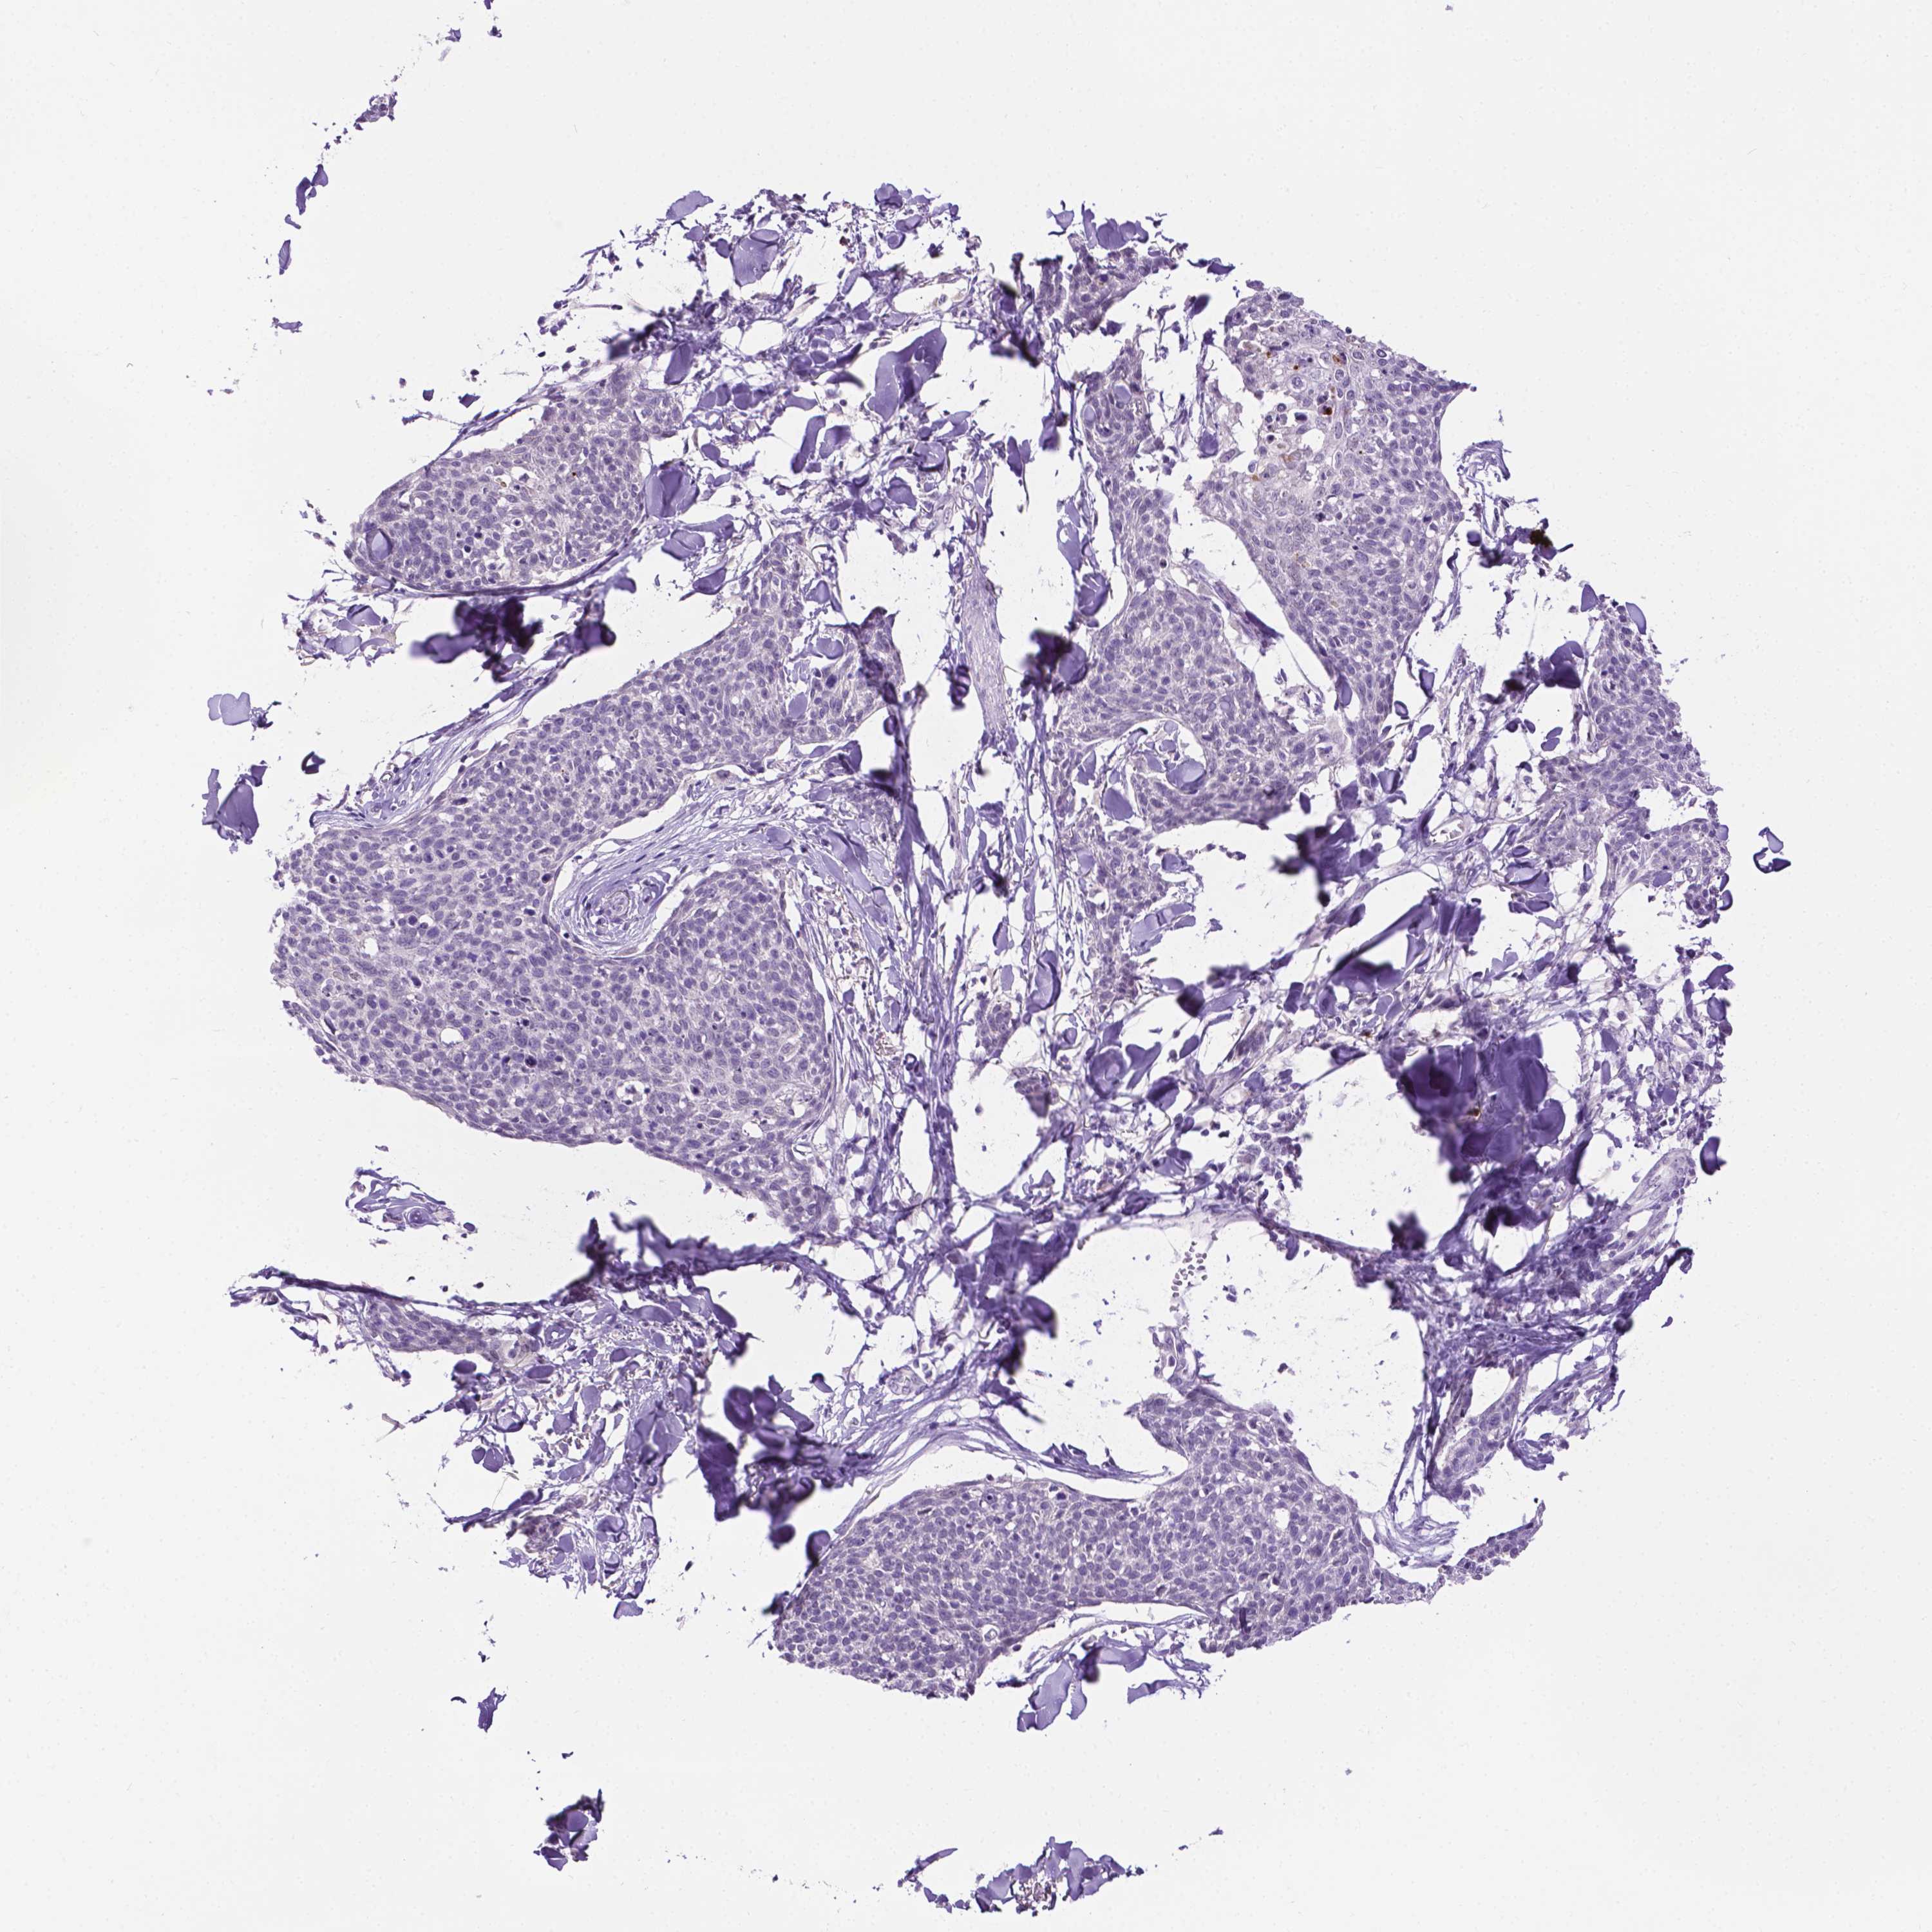

Basal cell and squamous cell cancer

SKIN CANCER - Protein expressioni

A mouse-over function shows sample information and annotation data. Click on an image to view it in a full screen mode. Samples can be filtered based on level of antibody staining by selecting one or several of the following categories: high, medium, low and not detected. The assay and annotation is described here.

Each image is clickable and will lead to virtual microscopy that enables deeper exploration of all samples and also displays staining intensity scores, fraction scores and subcellular localization as well as patient and tissue information for each sample.

Antibody HPA069097

Staining

High

Medium

Low

Not detected

Intensity

Strong

Moderate

Weak

Negative

Quantity

>75%

75%-25%

<25%

None

Location

Nuclear

Cytoplasmic/membranous

Cytoplasmic/membranous,nuclear

Squamous cell carcinoma, NOS